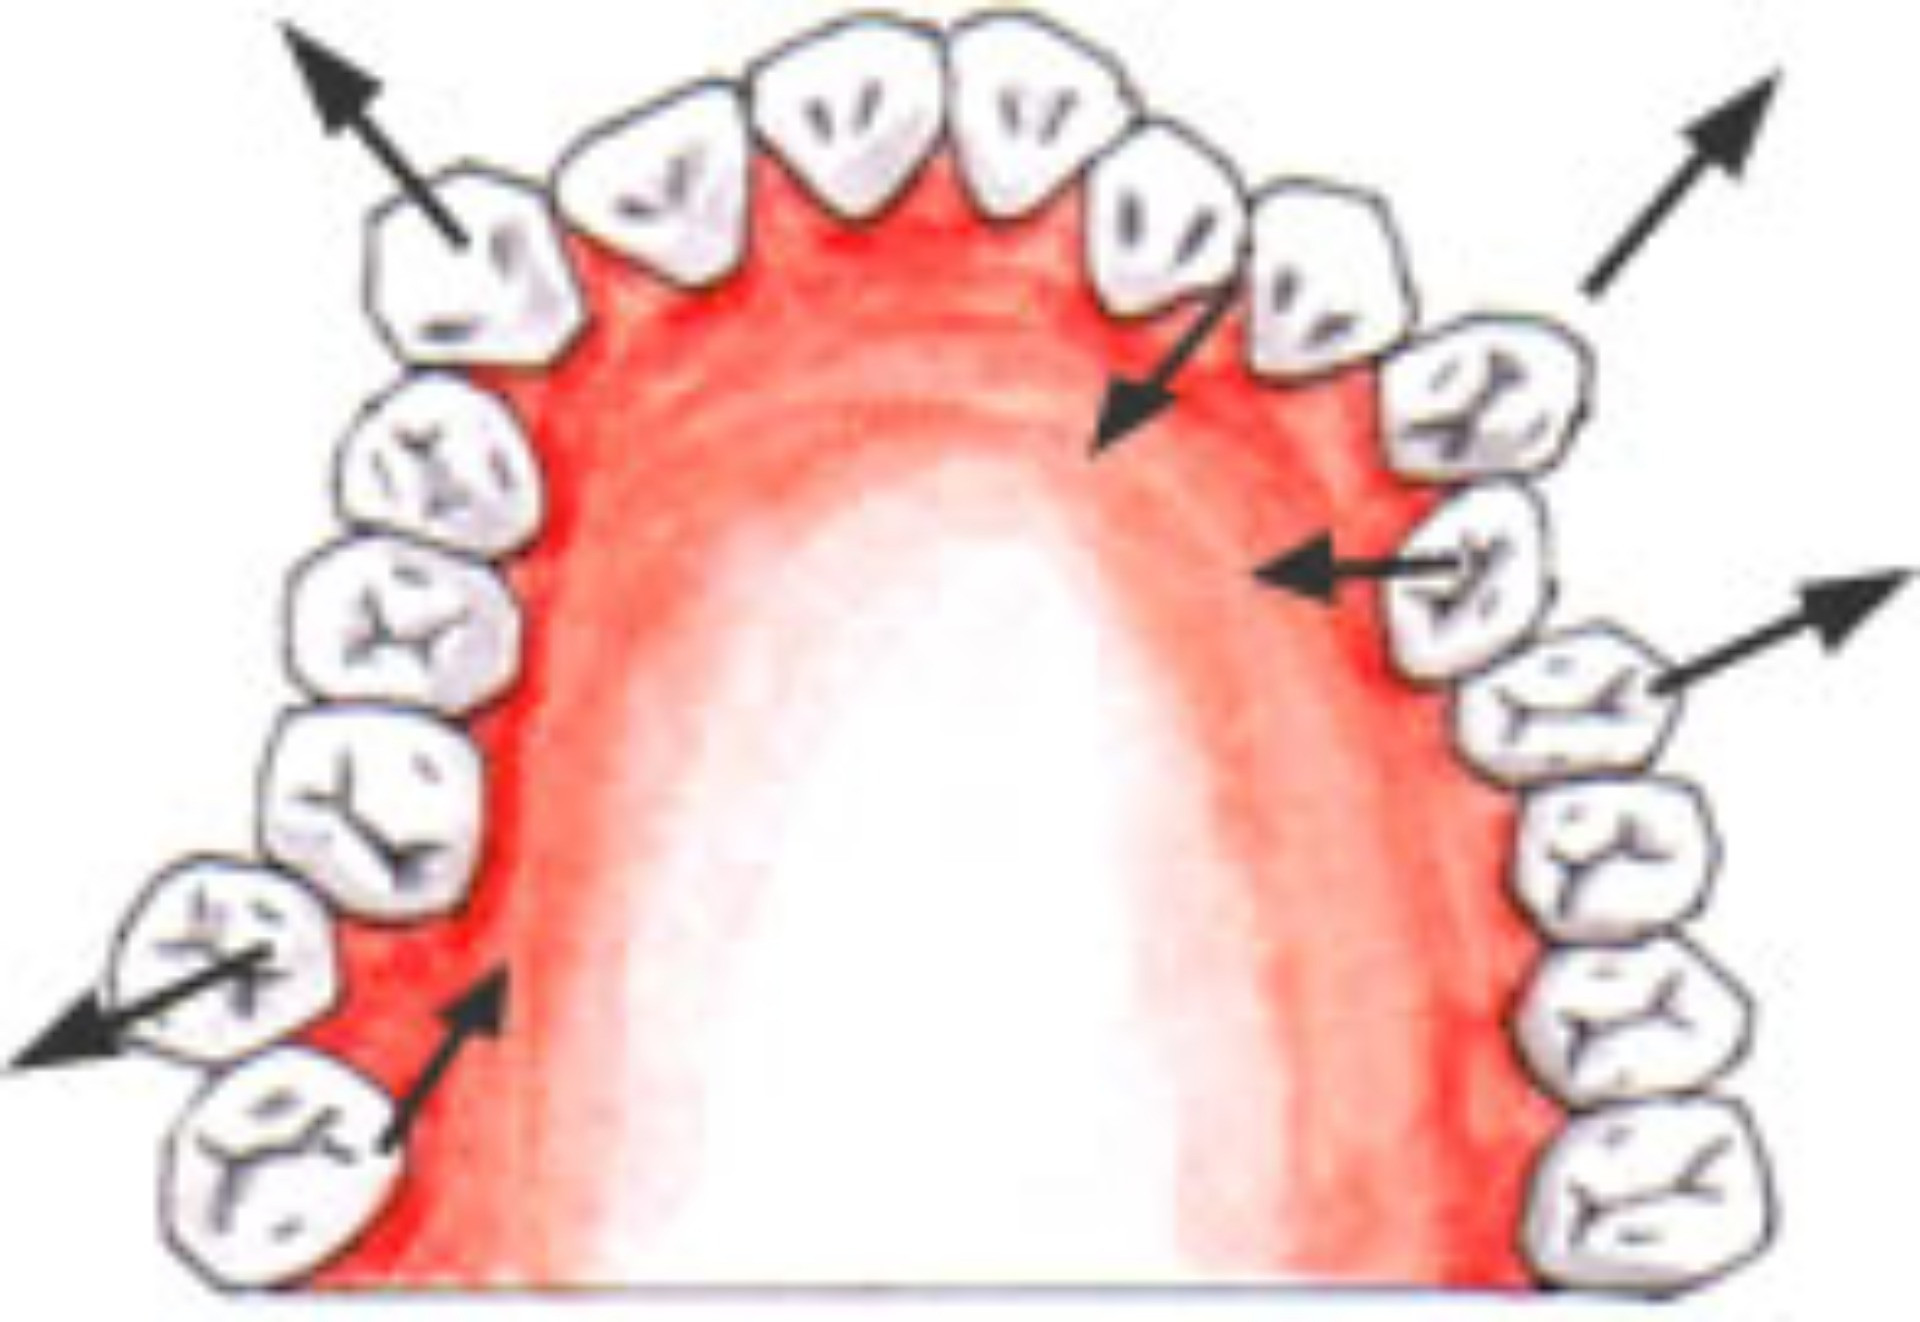

顎関節症 親知らずが手前の歯を押すことによって、歯並びを悪くする場合があります。

親知らずが手前の歯を押すことによって、歯並びを悪くする場合があります。